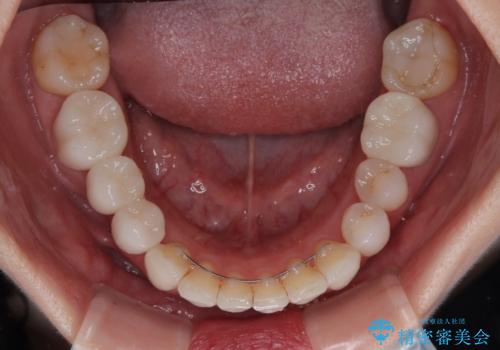

矯正治療自体はインビザラインで満足のいく仕上がりとなりました。

前歯は根管治療が必要となり、元々舌側に入り込んでいた左上2番目の歯は歯周外科処置により歯肉ラインを整えることとしました。

欠損部位は傾斜歯軸を起き上がらせることができたため、オールセラミッククブリッジにて補綴治療を行いました。

全顎的に満足のいく仕上がりとなりました。